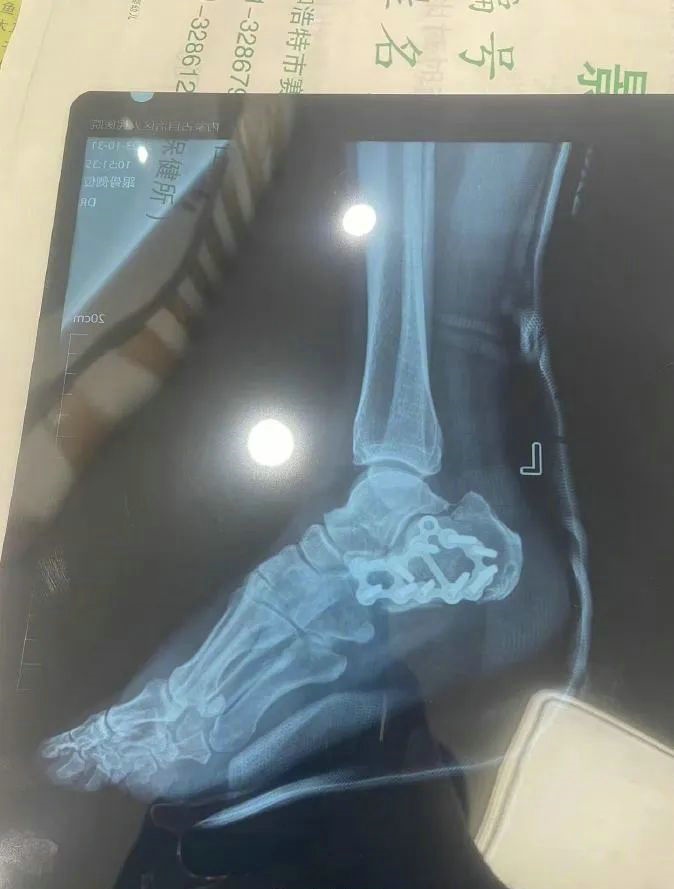

“那時(shí)候我剛工作了兩天,在第三天10月22日下午施工過程中從三層高的鐵架上摔了下來,導(dǎo)致30厘米左右的鋼筋刺穿我的右側(cè)臀部,左腳跟也粉碎性骨折,被送往內(nèi)蒙古自治區(qū)人民醫(yī)院救治,當(dāng)晚做了手術(shù)取出刺在右臀部的鋼筋,10月30日又進(jìn)行了左腳粉碎性骨折手術(shù)?!崩紫壬嬖V記者。

據(jù)雷先生介紹,當(dāng)時(shí)內(nèi)蒙古騰龍建設(shè)工程有限公司許經(jīng)理問過他賠付10萬元能否解決問題,他認(rèn)為這樣不太妥當(dāng)。“因?yàn)槲业淖竽_骨折還要進(jìn)行二次手術(shù),并且我臀部受傷不能坐著,只能包車回家,會(huì)產(chǎn)生一系列的費(fèi)用。”雷先生說。